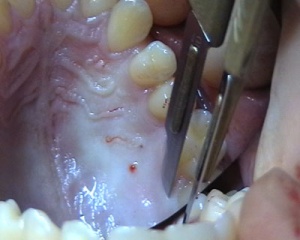

Patient présentant une récession gingivale au niveau d'une incisive mandibulaire qui est dûe à l'insertion haute du frein

Photos extraites de la vidéo :